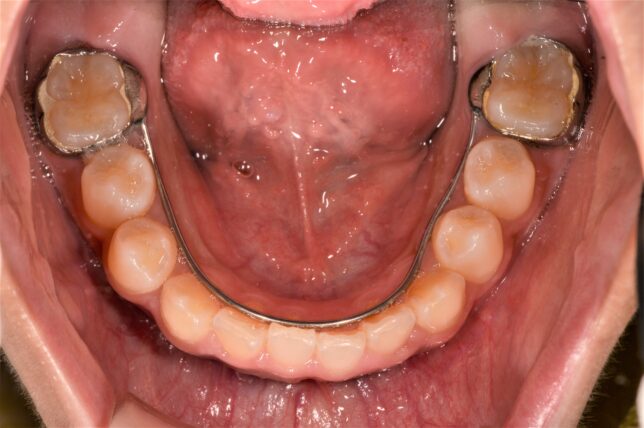

こんな場合は、下の画像のような取り外し式の矯正装置を使います。

治療後↓ 前歯の咬み合わせが、本来の咬み合わせになりました。

この装置を使うと、

年齢や歯の生え方にもよりますが、1~2か月で治ります。

咬み合わせが治った直後ですので、前歯が隙間(すきっ歯)になっていますが、通常ですと、ほぼ自然に閉じていきます。

この矯正装置は取り外し式装置なので、食事の時には外せます。

装着時間は長い方が良いのですが、学校には持っていかずに、家にいる時、食事以外ずっとつけていれば治ります。

寝る時もつけたままです。

この装置はプレオルソと違い、歯型を取って作成するので、歯型を取るというハードルはあるのですが、作ってしまえば、プレオルソより違和感は少なく、ほぼ問題なく、装着してくれます。

- 治療方法 床矯正装置

- 治療期間 1~2か月

- 費用の目安 66,000円~